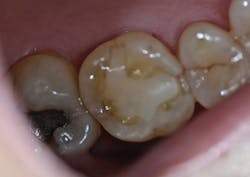

A 56-year-old male presented with pain on chewing. It was determined that several fractures had developed in the upper-left first molar, which was confirmed by bite-stick test (figure 8). A radiographic exam was within normal limits.

Figure 8: Patient presentation